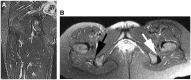

There is a continuum of hamstring injuries that can range from musculotendinous strains to avulsion injuries. Although the proximal hamstring complex has a strong bony attachment on the ischial tuberosity, hamstring injuries are common in athletic population and can affect all levels of athletes. Nonoperative treatment is mostly recommended in the setting of low-grade partial tears and insertional tendinosis. However, failure of nonoperative treatment of partial tears may benefit from surgical debridement and repair. The technique presented on this article allows for the endoscopic management of proximal hamstring tears and chronic ischial bursitis, which until now has been managed exclusively with much larger open approaches. The procedure allows for complete exposure of the posterior aspect of the hip in a safe, minimally invasive fashion.